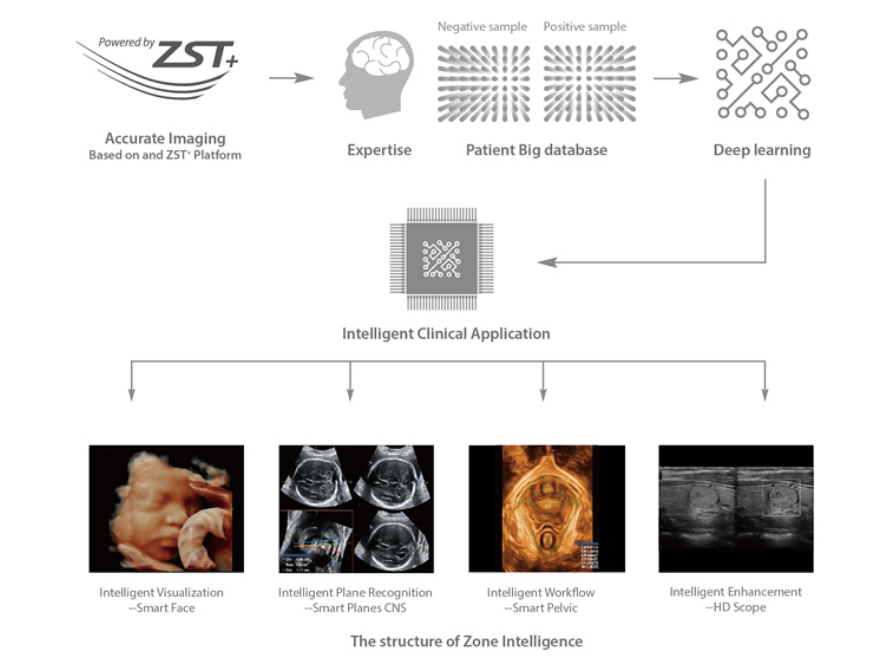

Powered by the channel data based ZST+ platform, the new Resona 6 with Zone Intelligence builds up a truly smart mechanism to deliver a new level of intelligence.The core of Zone Intelligence is deep learning that is based on big data base and Ultrasound expertise

As a result, it is able to provide multiple intelligent retrospective processing, leading to efficient and effective image visualization, plane recognition, measurement, and image enhancement .

MindrayŌĆÖs exclusive pioneering technology positions the Resona 6 as the industryŌĆÖs first ultrasound system to allow fully automatic and accurate detection of the most significant planes and frequently used measurements of fetal CNS, leading to intelligent diagnosis, improved throughput, and reduced user dependency.

Smart Planes CNS provides a user-friendly tool that greatly improves scanning efficiency through increased accuracy coupled with automated operation. With a simple button click on a 3D fetal brain volume image, the standard CNS scanning planes (MSP, TCP, TTP and TVP) and a range of related anatomical measurements (BPD, HC, OFD, TCD, CM and LVW) are obtained immediately.

Acquiring an optimal view of the fetal face in 3DUS is cumbersome and time-consuming. In some cases, it is impossible to get rid of the occlusions such as cord, placenta, uterus, and extremities. The new Resona 6 with Zone Intelligence provides a fast and intelligent optimization for fetal face with simple one-touch operation. It can immediately remove occlusions in the volume data and eliminate unwanted noise information, and generate an optimal view of the fetal face with minimized effort.

Realizing the increasing importance of ultrasound diagnosis on pelvic floor disorders, the new Resona 6 with Zone Intelligence provides a new solution to greatly simplify the operation procedures, and to minimize the exam time for a standardized evaluation on pelvic floor. With extremely simple user-interaction, it generates a standard coordinate system and automatically provides all related measurements within a few seconds.